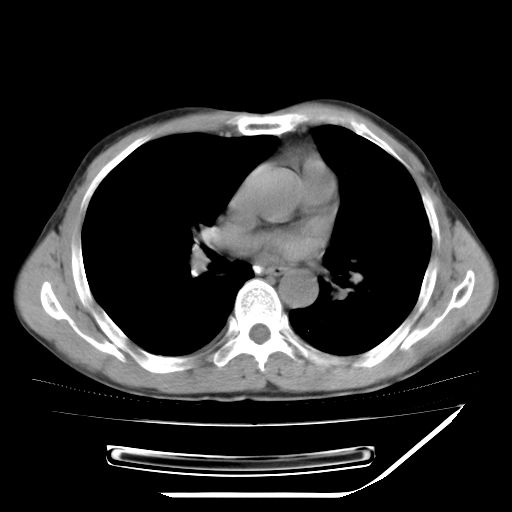

男,59岁,“结核性胸膜炎”30余年,胸部经常疼痛,多次x检查提示“肺部”炎症。腹部疼痛5日,b超提示:“肝内短管结石,余显示不清,建议进一步检查。”

两肺结核并右侧胸腔积液;脾脏、腹腔及腹膜后淋巴结结核[陈旧性];肝内胆管结石

胸部腹部都是结核(双肺。纵隔淋巴结,肝脏,脾脏,肠系膜)

均为结核所致,右侧少量胸腔积液